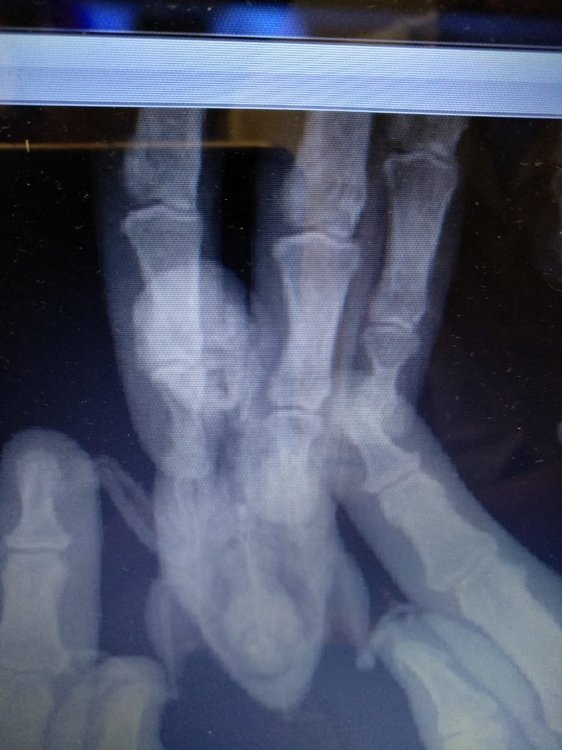

Добрый день! Все такт поехали мы к орнитологу в иваново.

Сделали рентген, врач осмотрел птичку. Поставил предварительный диагноз артроз. Подагру пока не ставит. На рентгене - отложения солей. Что удивительно, отложений больше на той лапке, на которую сейчас опирается больше. Сказал, что мы до этого все правильно лечились. Так что спасибо за советы!!! *THUMBS UP*

Разместите рентген, чтоб  @Zosia  посмотрела -- есть ли там артроз.

Вот наши рентгены. Только качество не очень.т.к. Фотка это